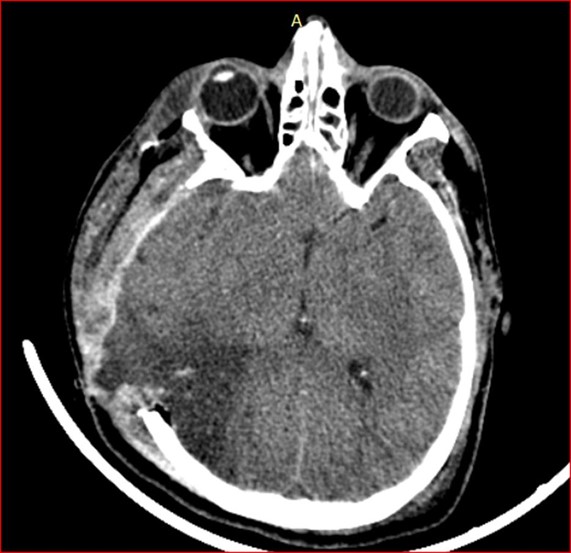

Figura 7. TAC de encéfalo simple (13/01/2023). Marcada concavidad del parénquima cerebral en el sitio de la hemicraniectomía descompresiva compatible con hernia paradójica. Se asocia a borramiento de surcos del hemisferio cerebral derecho con compresión del ventrículo lateral ipsilateral, con desviación de la línea media hacia la izquierda de 7 mm.

En este caso, el paciente desarrolló una hernia paradójica secundaria semanas después de la intervención quirúrgica inicial, manifestándose por colapso del parénquima cerebral bajo el defecto óseo y desviación de la línea media, hallazgos característicos que fueron evidentes en la tomografía cerebral del 13 de enero. La cronología y evolución del cuadro clínico coincide con lo descrito en la literatura, donde este tipo de herniación puede aparecer de forma tardía y empeorar progresivamente si no es reconocida a tiempo.(13, 14)